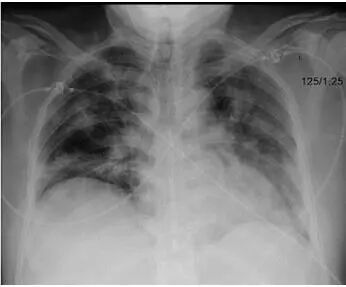

文献5:中南大学湘雅二医院,Clinical and imaging characteristics of hospitalized patients with severe influenza A (H1N1) virus infection and concomitant pneumonia (a report of 39 cases and literature review)。

还是那句老话,多发,下肺为主,斑片、实变、磨玻璃,少胸水,无空洞。